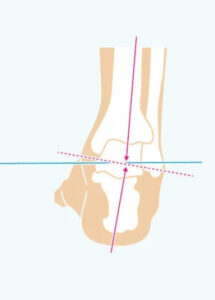

Hyperpronation (Verification) indicates excessive ‘falling’ of the inner arch of the foot inwards during walking or running. It is most often caused by muscle weakness, inadequate footwear or genetic predispositions. It can lead to pain in the feet, ankles, knees, hips and spine. It is also recognized by the wear of the gon on the inside of the shoe.

Hyper-supplementation (Oversuperation) indicates over-reliance on the outer edge of the foot while walking, with a pronounced inner vault. Causes can be muscle imbalance, inappropriate footwear or genetics. It can cause pain throughout the kinetic chain – from the foot to the spine. It is also recognized by the wear of the joon on the outside of the shoe.